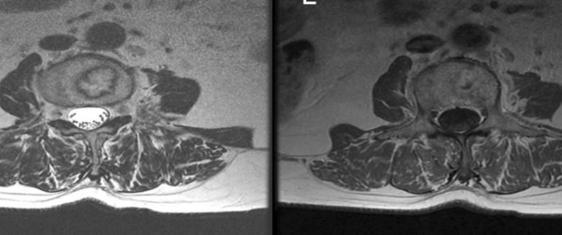

诊断许莫氏结节主要依靠影像学检查,如X线、CT和MRI。典型的影像表现包括椎体终板局限性缺损、椎体内低密度灶等。然而,值得注意的是,许莫氏结节也可能有不典型表现,如穿通性、囊性或脂肪性结节,这需要医生具备丰富的经验和专业知识来准确诊断。